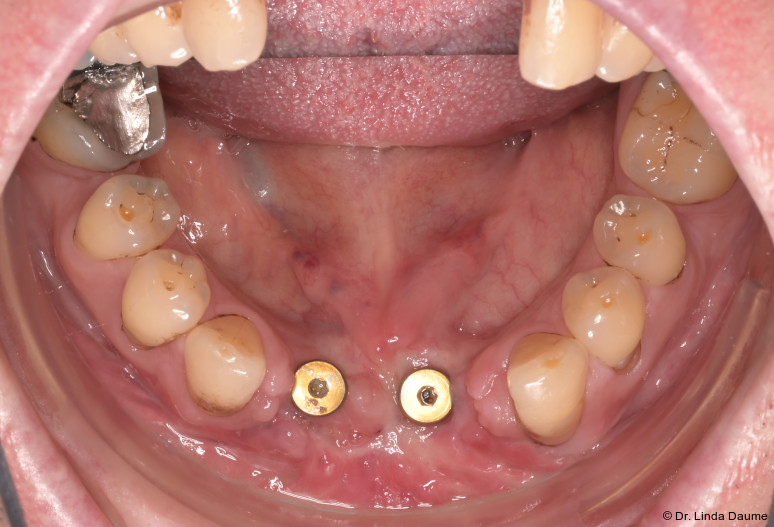

Ein 60-jähriger Patient stellte sich mit einem ausgeprägten, traumabedingten Knochen- und Weichteildefizit in der Unterkieferfront vor (Abb. 1a+b). Es bestand der Wunsch nach einer festsitzenden implantatprothetischen Versorgung. Im Jahr 2021 war es durch einen Fahrradsturz zu einer Unterkieferfraktur gekommen, die alio loco mehrfach voroperiert worden war. Im Zuge der Behandlung waren die Zähne 32-42 verloren gegangen.

Nach einer Latenzphase von sieben Tagen begann die Distraktion mit 1 mm pro Tag, aufgeteilt in mehrere Einzelaktivierungen unter engmaschiger Kontrolle. Nach Erreichen der vorgesehenen Endposition begann die Konsolidierungsphase (Abb. 4). Der Distraktor wurde nach acht Monaten entfernt und es erfolgte die Implantation in Regio 32 und 42 mit lokaler Augmentation (Abb. 5a+b). Nach einer weiteren Einheilphase von fünf Monaten wurden die Implantate freigelegt und das Weichgewebe mittels eines freien Schleimhauttransplantats vom Gaumen optimiert. Die prothetische Versorgung konnte anschließend festsitzend mit einer implantatgetragenen Brücke von 32-42 realisiert werden (Abb. 6).